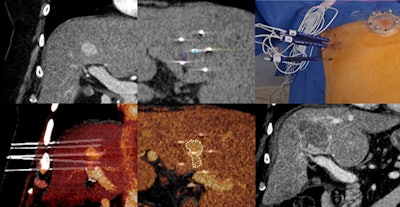

Advances in interventional radiology, including robot-assisted procedures for abdominal cancers, will be addressed by Prof. Laurent Milot, PhD, professor of radiology at the University of Lyon and an interventional radiologist at Edouard Herriot Hospital, Lyon.

“Robotic-assisted interventional radiology procedures are on the rise, theoretically allowing us to better democratize and standardize even the most complex techniques,” he said. “Robotic solutions can also harbor advanced AI-driven planning solutions, potentially improving patient outcomes.”

Corresponding treatment of a central hepatocellular carcinoma (HCC) shows the precision achieved with the help of the robot, even for junior practitioners. Courtesy of Prof. Laurent Milot.

French radiologists, researchers, and companies are amongst the pioneers in the development and evaluation of robotics in this field, with early research showing very encouraging results, Milot emphasized. Ablation techniques continue to be the mainstay in the treatment of abdominal cancers, he added.